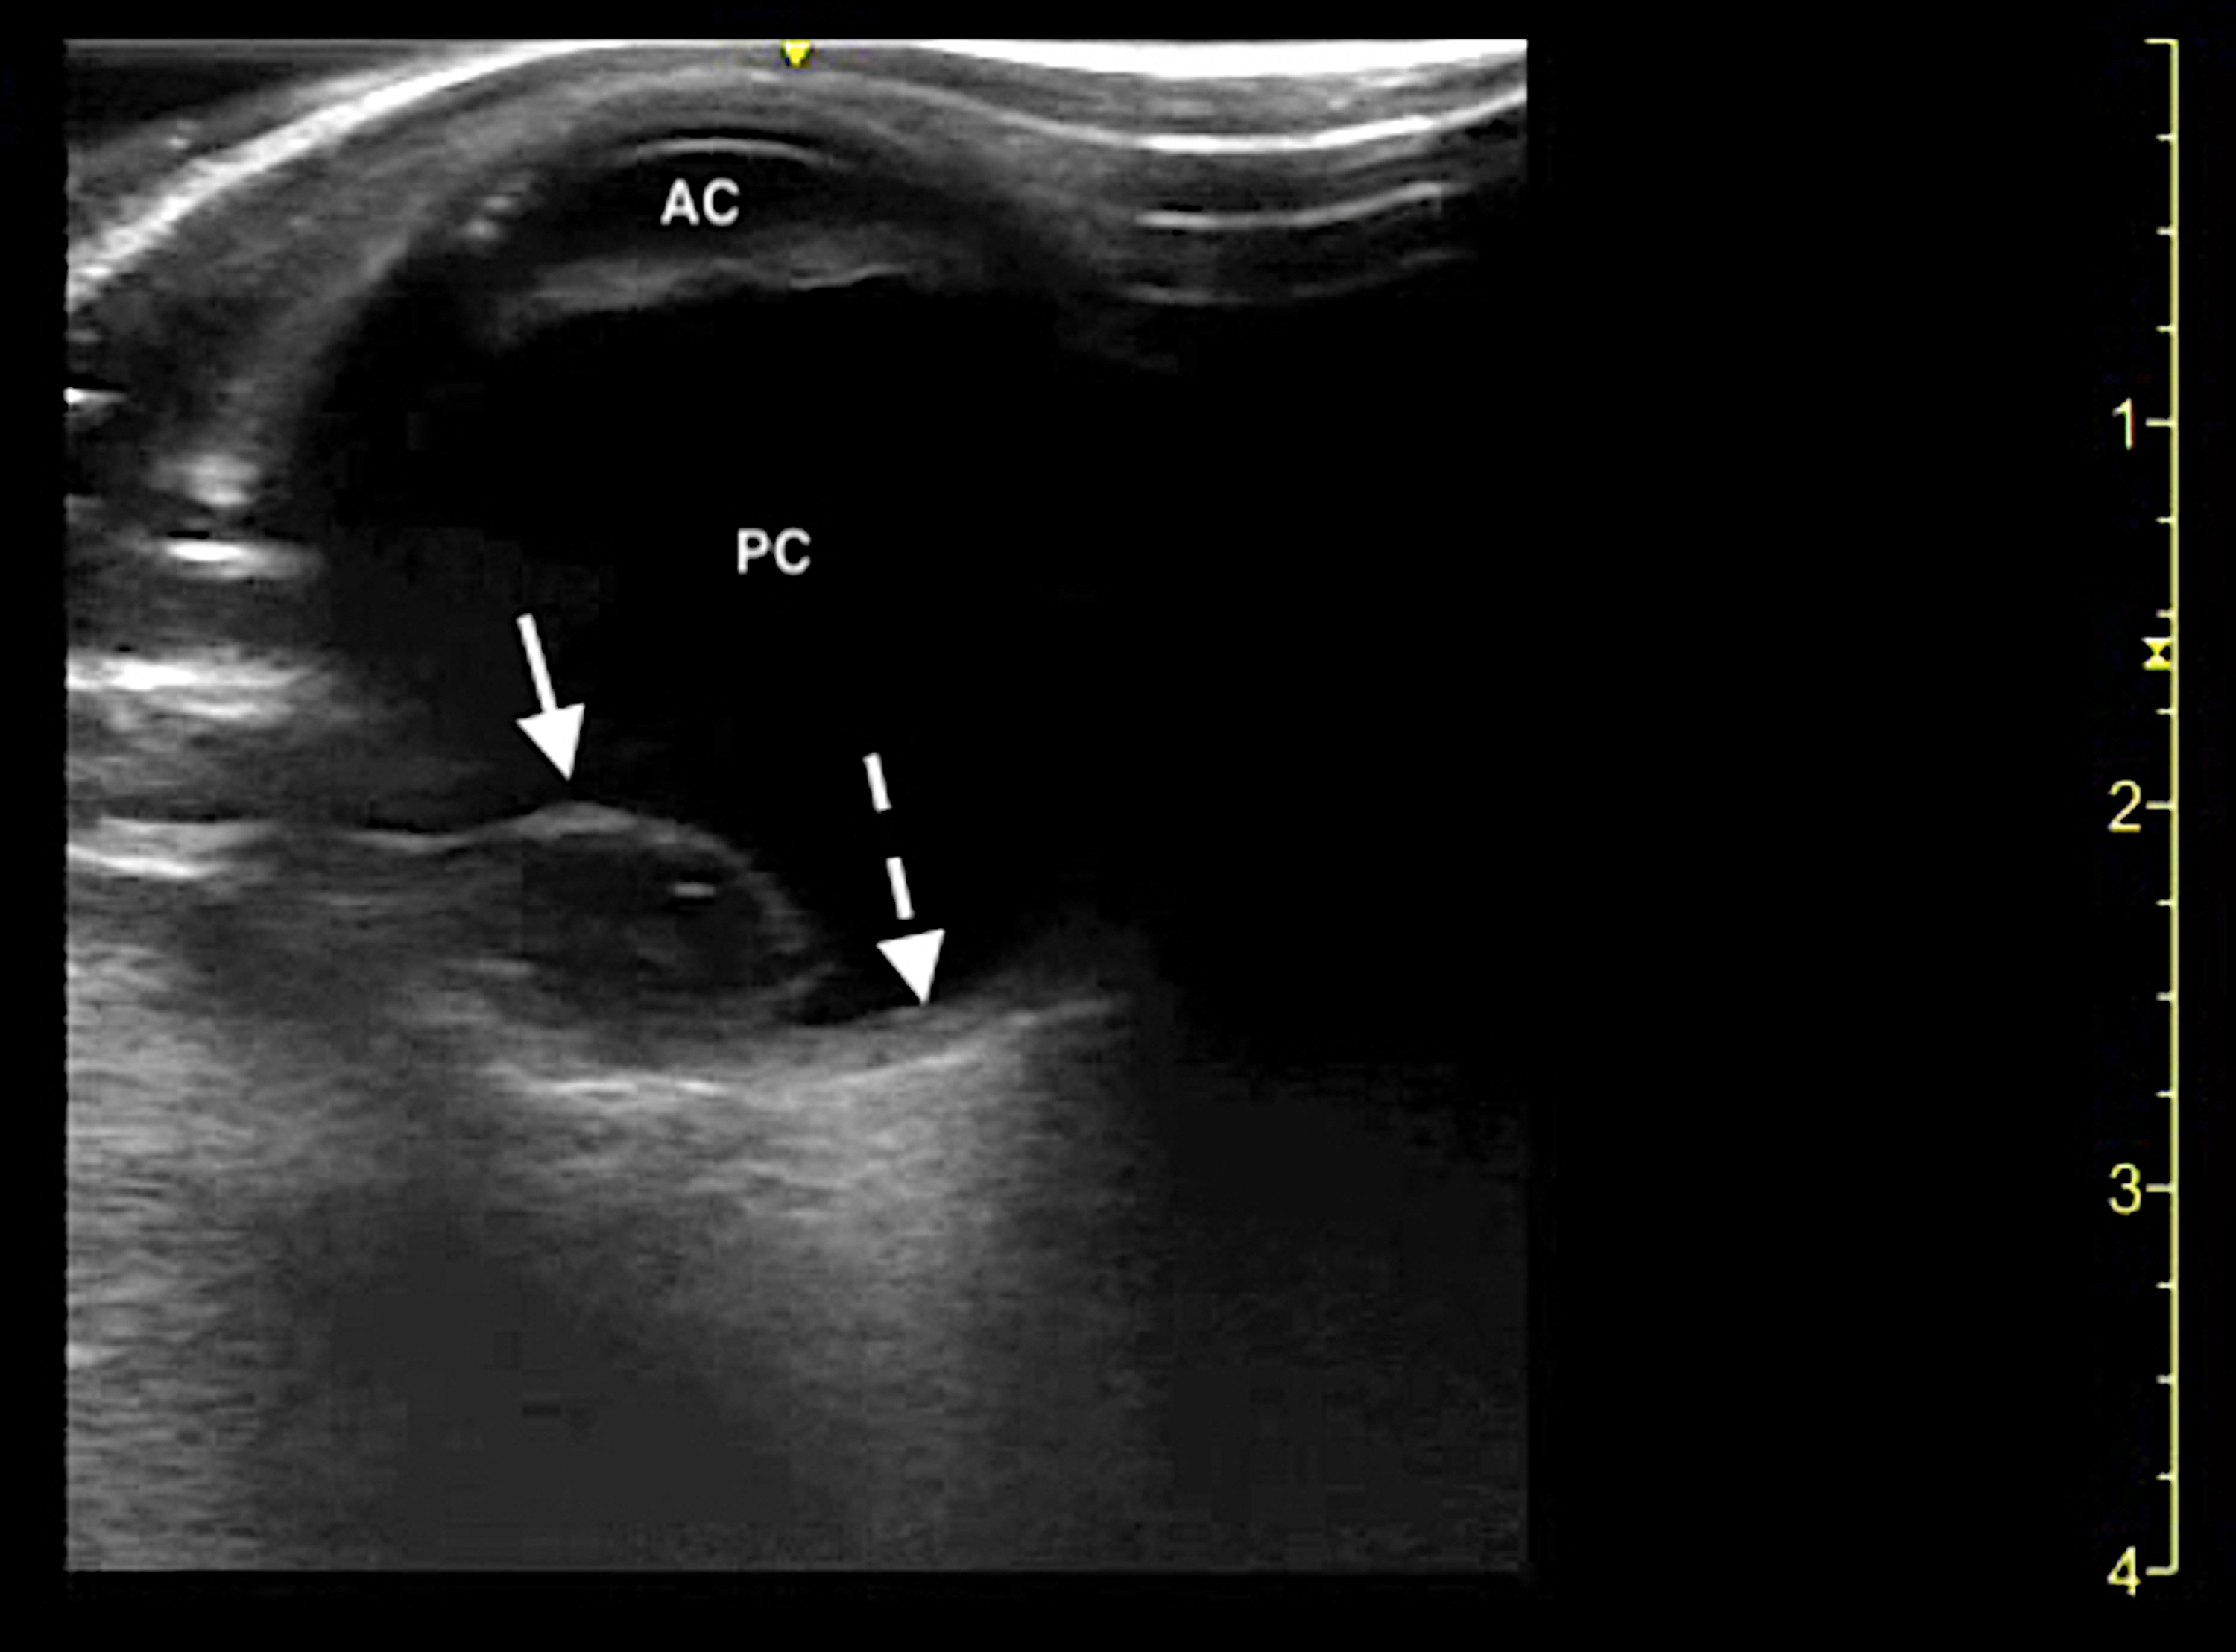

From www.cureus.com

Cureus Bedside Ocular Ultrasound Diagnosis of a Traumatic Lens Eye Lens Dislocation ectopia lentis happens when the lens in your eye is dislocated or moved out of its normal place. a dislocated lens is a lens that has moved out of position because some or all of the supporting ligaments. The lens is defined as luxated (dislocated). in partial zonular loss or weakness without complete posterior dislocation, a variety. Eye Lens Dislocation.